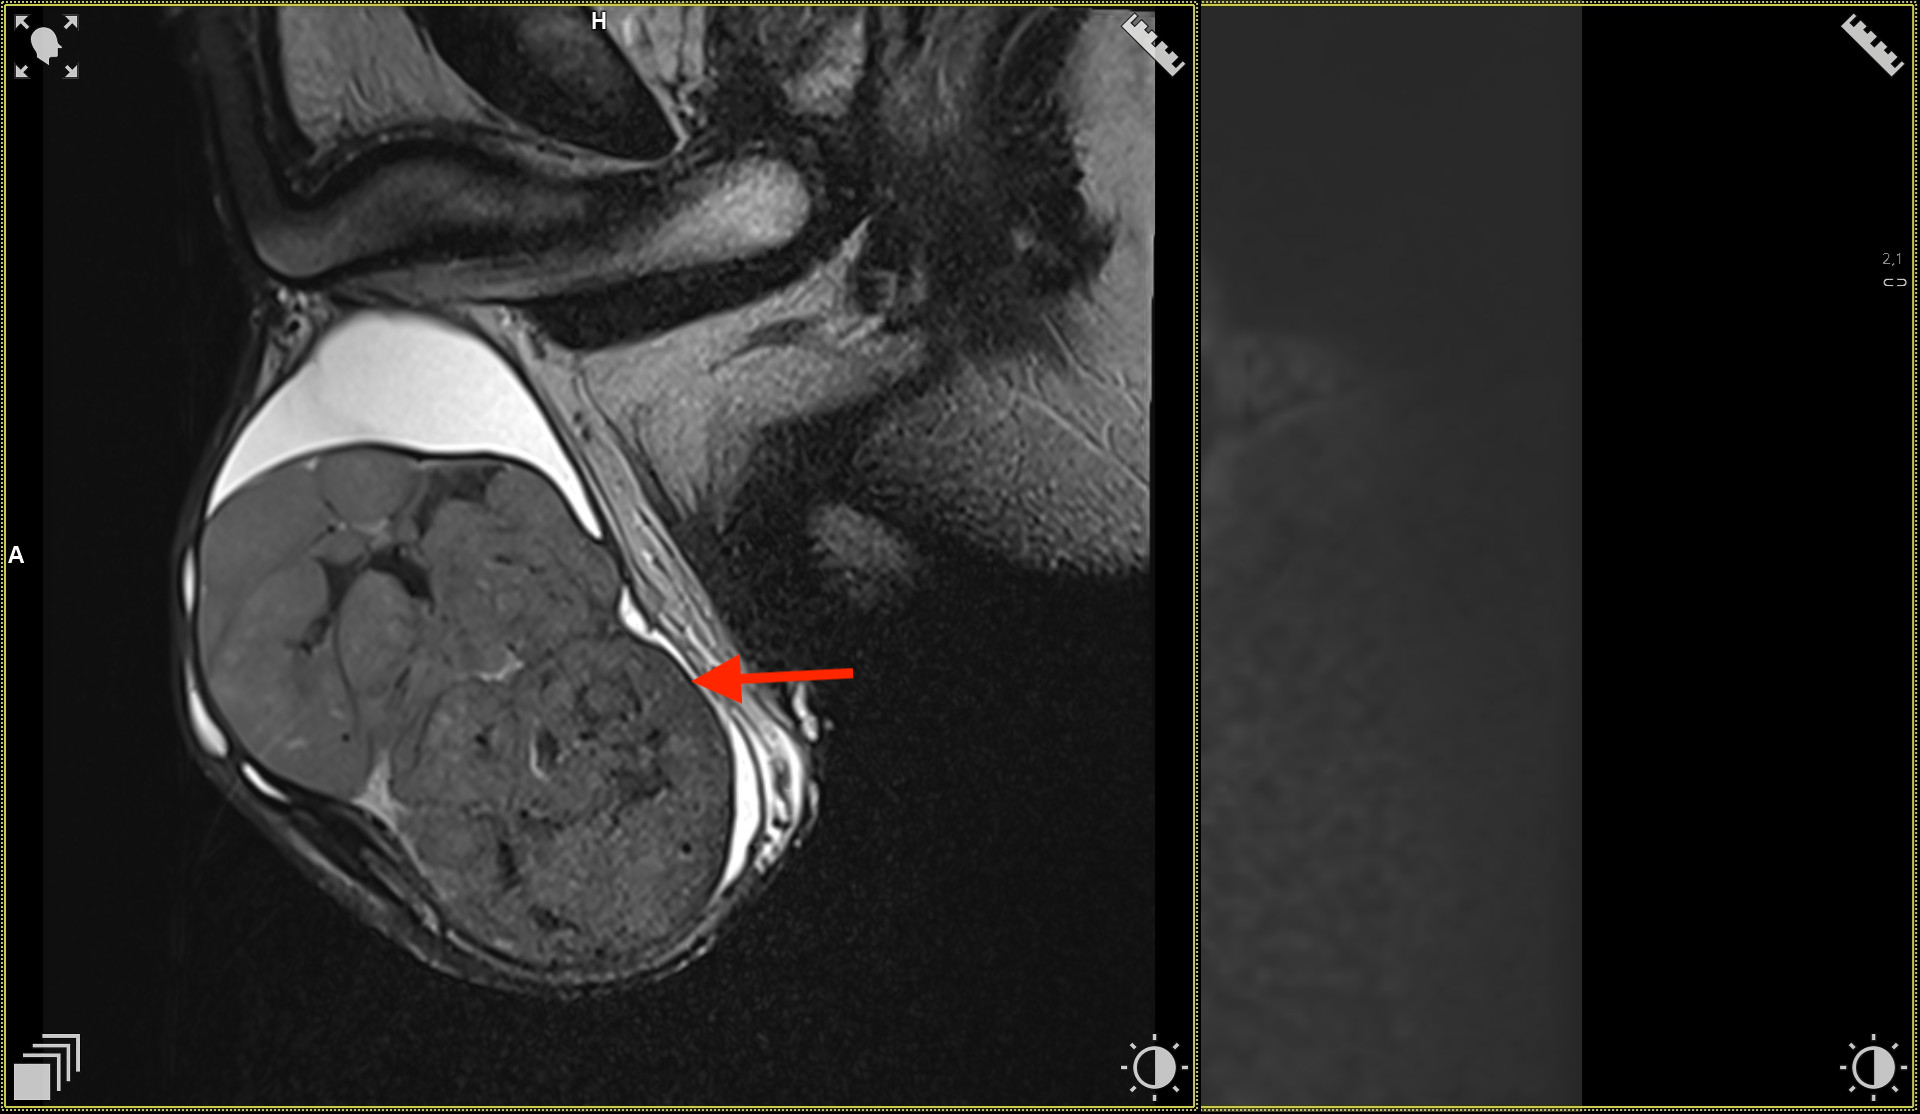

Obrazy w sekwencjach DWI w płaszczyźnie osiowej. Widoczna zmiana w jądrze lewym.

Obrazy w sekwencjach T2 w płaszczyźnie osiowej. Widoczna zmiana w jądrze lewym.